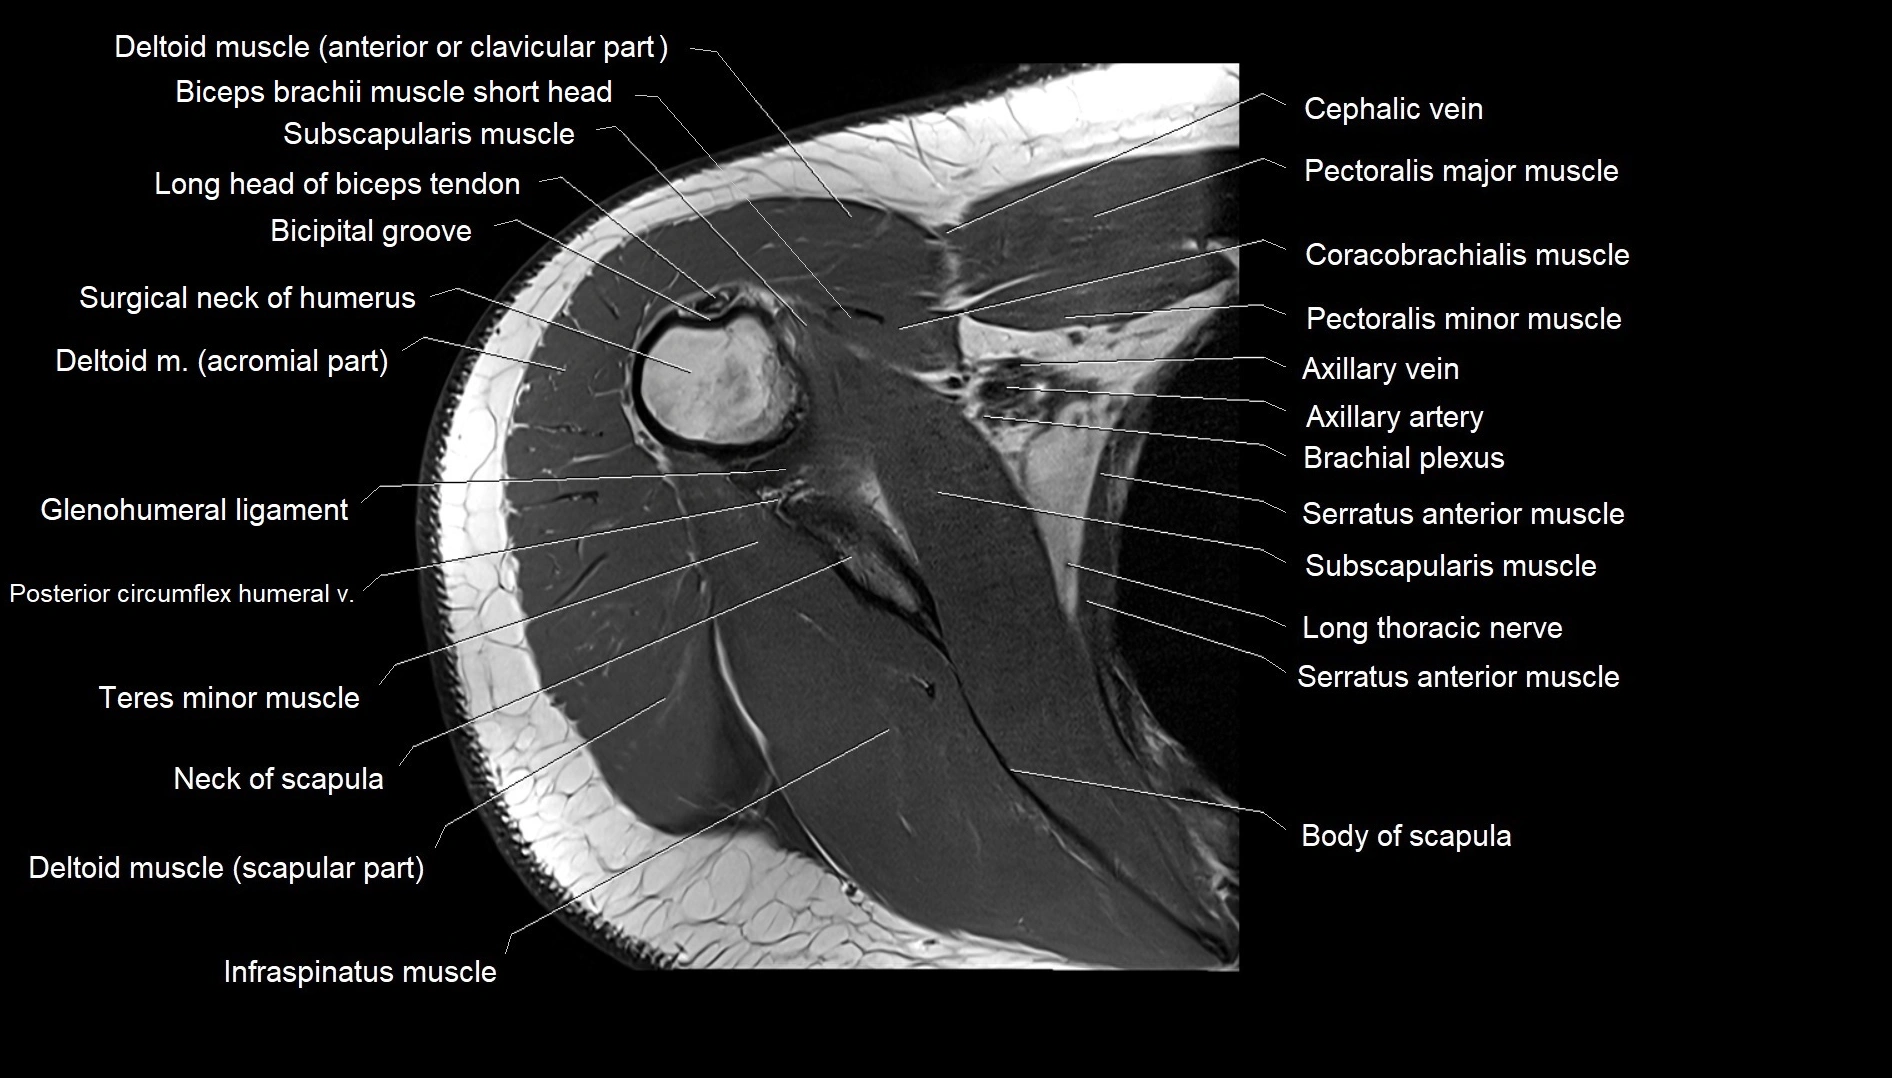

MRI images

image